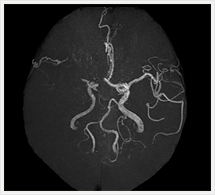

心・血管造影検査

心・血管の造影検査とは?

X線不透過物質である、ヨード造影剤を使用して血管の形態、血流状態を連続的に撮影することにより、動脈あるいは静脈の病変を診断する検査法です。

先天性心疾患、血管性病変(動脈瘤・静脈瘤・動静脈奇形・動脈硬化、あるいは血栓症による血管の狭窄および閉塞など)の診断や、脳、および四肢などの腫瘤性病変の診断などを目的に行われています。

画像紹介(頭頚部血管編)

画像は、頚動脈の狭窄部分に“ステント”と呼ばれる金属性の網状の筒を留置して、血管を正常径まで拡張させる手術です。この治療は、内膜剥離術と比較して非侵襲的であり、高齢者やいろいろな合併症を持った方にも負担を少なくして行うことができます。術後の安静期間や入院期間も短いのが特徴です。